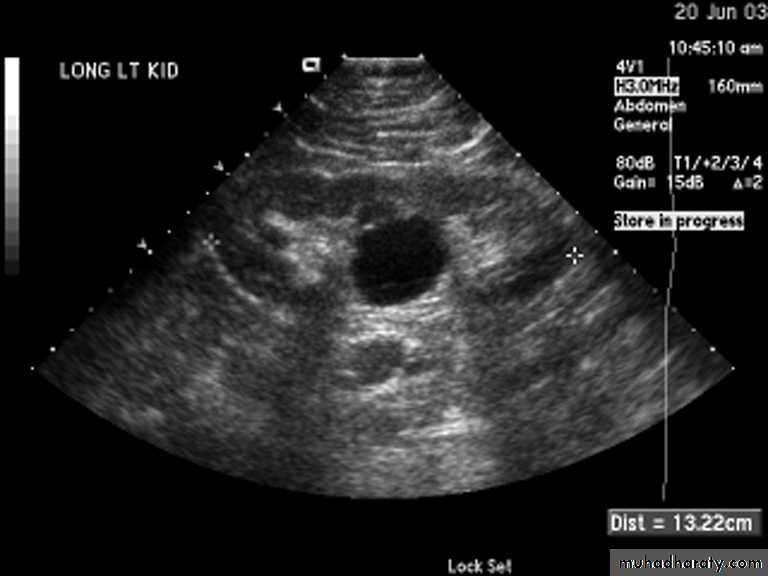

Simple (solitary) renal cyst

Common condition.Single or multiple.

Uni or bilateral.

Congenital or acquired.

Usually asymptomatic. In 10% symptomatic: pain, heaviness, infection, bleeding inside the cyst or pressure effect on the ureter causing hydronephrosis.

Examination: usually –ve, big cyst cause painless loin mass, & painful if complicated by bleeding or infectionU/S: echo free area (cystic lesion).

CT scan &MRI: are diagnostic.